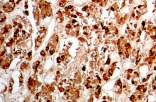

CE/IVD antibodies for immunohistochemistry (IHC) in neuropathology are validated in vitro diagnostic reagents used to detect specific neuronal and glial antigens in formalin-fixed paraffin-embedded (FFPE) tissue. Peer-reviewed neuropathology literature supports their role in improving reproducibility and diagnostic accuracy in central nervous system (CNS) diseases, including brain tumors and neurodegenerative disorders.

Targeted proteins such as GFAP, OLIG2, NeuN, synaptophysin, neurofilament, and Iba1 reflect astrocytic, oligodendroglial, neuronal, and microglial lineages. Their expression patterns are widely used in peer-reviewed studies to define CNS cell identity, differentiation state, and neuroinflammatory or degenerative processes.

CE/IVD IHC antibodies support CNS tumor classification (gliomas, embryonal tumors, metastases), assist in differential diagnosis, and help identify proteinopathies associated with Alzheimer’s disease and other neurodegenerative conditions. They are routinely used in biomarker panels for tumor grading and diagnostic stratification in neuro-oncology.